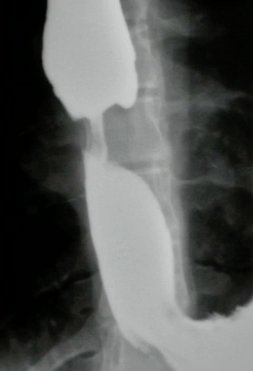

What is your diagnosis in this patient who presented with heart burn?

Sliding hiatal hernia. Note that the mucosal ring is > 2 cm superior to the diaphragm.